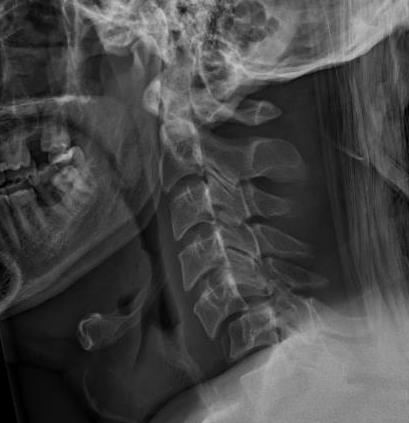

Unilateral facet joint dislocation on xray - 25% subluxation on lateral X-ray (<50%)